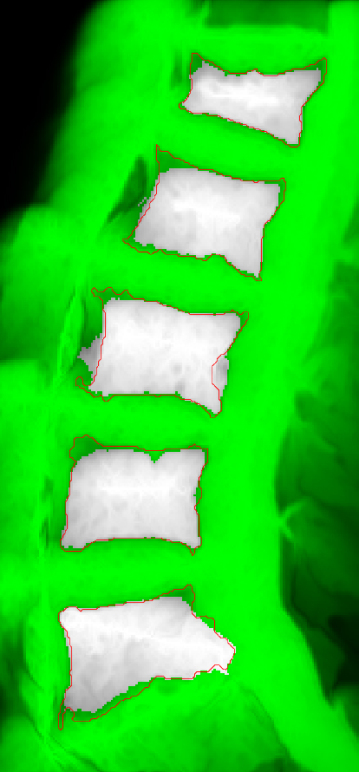

Spinal diseases are quite usual worldwide and can cause significant loss of function and quality of life [1]. A very recurrent disease among older adults is the Vertebral Compression Fracture (VCF), which, in general, is caused by osteoporosis (benign) or bone metastasis (malignant) [2, 3, 4]. In general, VCFs are early detected or diagnosed based on shape or texture using Magnetic Resonance Imaging (MRI) [5, 6, 3, 7]. Usually, a specialist manually segments the Region of Interest (ROI) to aid the diagnose, which can be time consuming and prone to errors, due to inter and intra-subject variability and the subjective judgment that is employed [8].

However, it incorporates expert knowledge gained over several years. Figure 1 shows an example of manual segmentation over five lumbar vertebral bodies (L1-L5).

The semi or automatic segmentation of VCFs is a challenging task, due to non-homogeneous gray-scale intensities within the same vertebral body (for example, L5 in Figure 1). To overcome this issue, several one-seed-point approaches have been proposed. In [3] is presented the VBSeg method, which employs superpixels, region growing and Otsu threshold. Region growing techniques are used in [9], such as, snakes (Chan-Vese), Otsu and fuzzy c-means clustering, in order to compose a cooperative strategy for a dynamic ensemble of classification models. Although both works have presented very promising results, the VBSeg method presents a low segmentation performance on VCFs (61% and 74% Jaccard coefficient for malignant and benign VCFs, respectively). The cooperative strategy for classification still depends on the ground-truth.